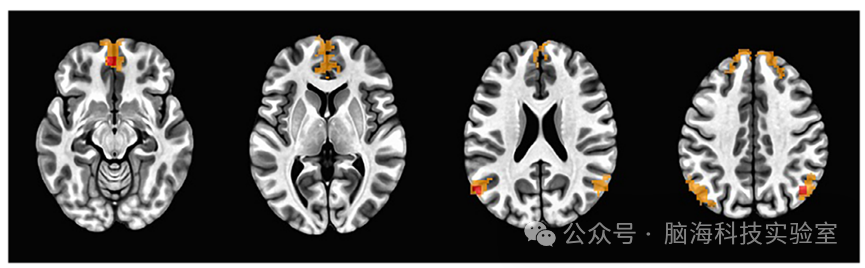

使用z分数进行全脑3dttest++,以确定与后扣带回种子显著连接的ROI,以索引样本中的DMN连接。在p<0.01假发现率(FDR)校正后得到的DMN连接图(图1)用于识别DMN特定的ROI。分析确定了四个与后扣带回种子显著连接的ROI,包括完整的DMN图、内侧前额叶皮层(MPFC x,y,z=-3,51,-12)、左顶叶皮层(LPAR x,y,z=-58,-67,25)和右顶叶皮层(RPAR x,y,z=45,-67,38)。接下来,在每个ROI的峰值体素周围创建5mm半径的球形种子。使用3dROIstatsROI种子以及完整的DMN图中提取平均z分数,并导出以进行组分析,以检查DMN内的FC(即,每个ROIz分数)与心肺健康之间的关系。

图片

分析中包含的感兴趣区种子上的DMN地图的轴向视图。DMN,默认模式网络;投资回报率,感兴趣区域。